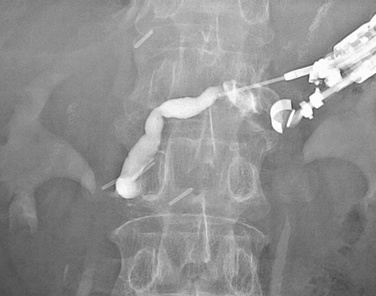

3) EUS- cyst drainage  (EUS-CD;のう胞ドレナージ)

• EUS-cyst drainageの画像1

• EUS-cyst_drainageの画像2

• EUS-cyst_drainageの画像3

• EUS-cyst_drainageの画像4